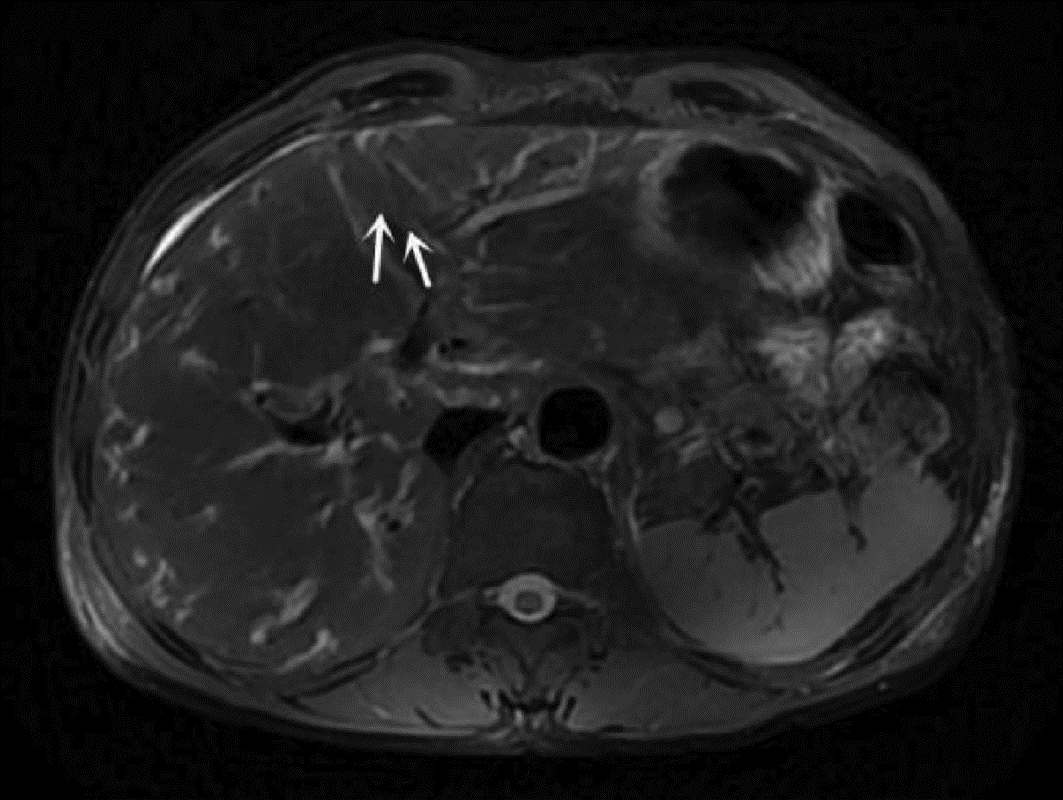

JIANG SM, HUANG JK, LIANG QD, et al. Multiple low-density foci in the liver with pulmonary embolism diagnosed as clonorchiasis: A case report[J]. J Clin Hepatol, 2020, 36(10): 2285-2287. DOI: 10.3969/j.issn.1001-5256.2020.10.027.

江善明, 黄继康, 梁其栋, 等. 肝内多发低密度灶合并肺栓塞诊断为肝吸虫病1例报告[J]. 临床肝胆病杂志, 2020, 36(10): 2285-2287. DOI: 10.3969/j.issn.1001-5256.2020.10.027.

HUANG JH, ZHENG FP, XU HX, et al. A case of atypical liver fluke disease with low-density space-occupying changes in the liver[J]. China Trop Med, 2019, 19(5): 501-502. DOI: 10.13604/j.cnki.46-1064/r.2019.05.25.

黄嘉煌, 郑凤屏, 徐慧璇, 等. 以肝脏呈低密度占位性改变的1例非典型肝吸虫病例报道[J]. 中国热带医学, 2019, 19(5): 501-502. DOI: 10.13604/j.cnki.46-1064/r.2019.05.25.